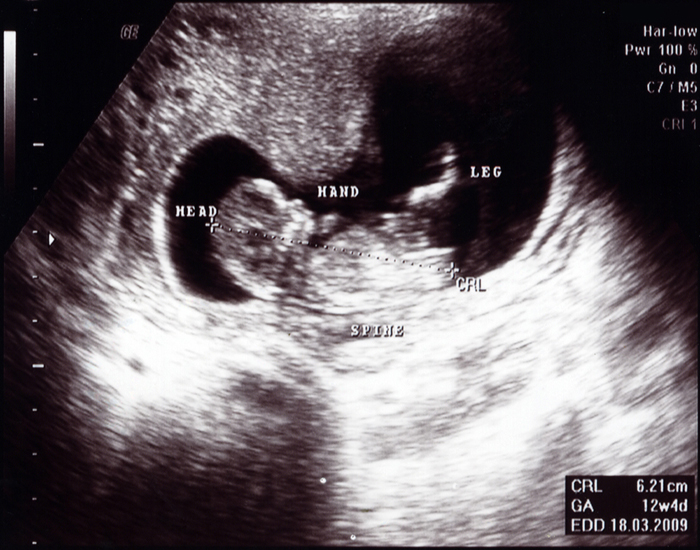

6 aylık gebelik görüntülerinde vücudu orantılı görünür. Kız bebeklerde bu hafta yaklaşık 6 milyon yumurta oluştu. 17 hafta hamilelikte bebeğin görüntüsü resimde olduğu gibi olacaktır. 6 haftalık (1 ay 1 haftalık) gebelik. Hafta itibarı ile artık bebeğinizin görüntülerini, kese boyunu ultrasonla görebilirsiniz. Hamilelikte ilk üç ayda sana neler lazım:

Hafta bebek gelişimi, 7 haftalık bebek görünümü, 7 haftalık bebek nasıl olur, 7 haftalık hamilelik, gebelikte 7 hafta bebeğin boyu ve kilosu, 7. On dördüncü hafta gebelik ultrason görüntüsü buna benzer olabilir ama değişik olursa da endişelenme. 8 haftalık gebelikte görülen semptomlar rahmin büyüdükçe şikayetler artacak.

Bebeğim ultrason görüntüleri 13 hafta YouTube

14 haftalık bebek ultrason görüntüsü. Hafta itibarı ile artık bebeğinizin görüntülerini, kese boyunu ultrasonla görebilirsiniz. 19 haftalık ultrason görüntüleri ve 19.hafta bebek gelişimi ile ilgili görüntüler bu dönemdeki değişiklikleri size görsel olarak da anlatacaktır.